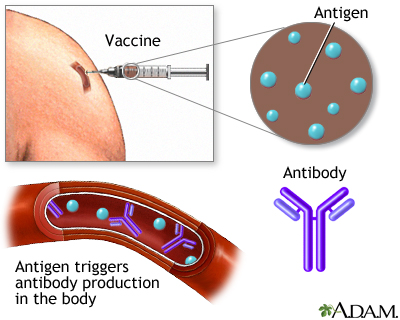

Your body is designed to protect you from infections. When you are exposed to a virus, bacterium, or other microbe, your immune system actually "learns" from the experience. The next time your body is exposed to the same microbe, your immune system often recognizes it and sets out to destroy it.

During immunization, you are exposed to an inactive/weakened microbe or a very small and safe amount of part of a microbe. Your body's immune system responds to the vaccine by making substances called antibodies. If you are exposed to the microbe itself at a later time, the antibodies will kill the microbe and prevent infection or you may have a milder infection.